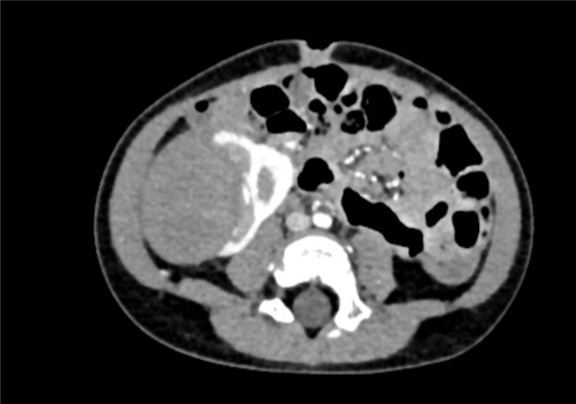

下腹部CT动态增强扫描 肾母细胞瘤化疗后,右肾巨大占位,较前范围减小,请结合临床。

术前CT检查:

动脉期

静脉期

平衡期